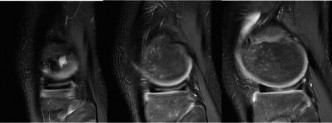

Following the plain radiographs, an urgent Magnetic Resonance Imaging study of the entire right femur with and without intravenous gadolinium contrast was executed to delineate the exact anatomical extent of the lesion.

The MRI protocols included T1-weighted, T2-weighted fat-suppressed (STIR), and T1 post-contrast sequences. The T1-weighted coronal sequences were critical for mapping the intramedullary extent of the tumor, which replaced the normal high-signal fatty marrow with intermediate-signal tumor tissue. The tumor measured 11.5 centimeters in craniocaudal dimension. Crucially, the MRI confirmed that the distal extent of the tumor abutted, but did not frankly cross, the open distal femoral physis.

Axial T2-weighted sequences demonstrated a large, heterogeneous, hyperintense extraosseous soft tissue component. The neurovascular bundle (popliteal artery and vein) was displaced posteriorly but maintained a visible fat plane, indicating it was not directly encased by the tumor—a vital finding for potential limb salvage. Whole-bone imaging confirmed the absence of intramedullary "skip" metastases.

Concurrently, a high-resolution Computed Tomography scan of the chest was obtained to evaluate for pulmonary metastases, which are the most common site of systemic dissemination in osteosarcoma. The CT chest was negative for pulmonary nodules. A Technetium-99m whole-body bone scan showed intense radiotracer uptake localized solely to the right distal femur, ruling out synchronous skeletal lesions.